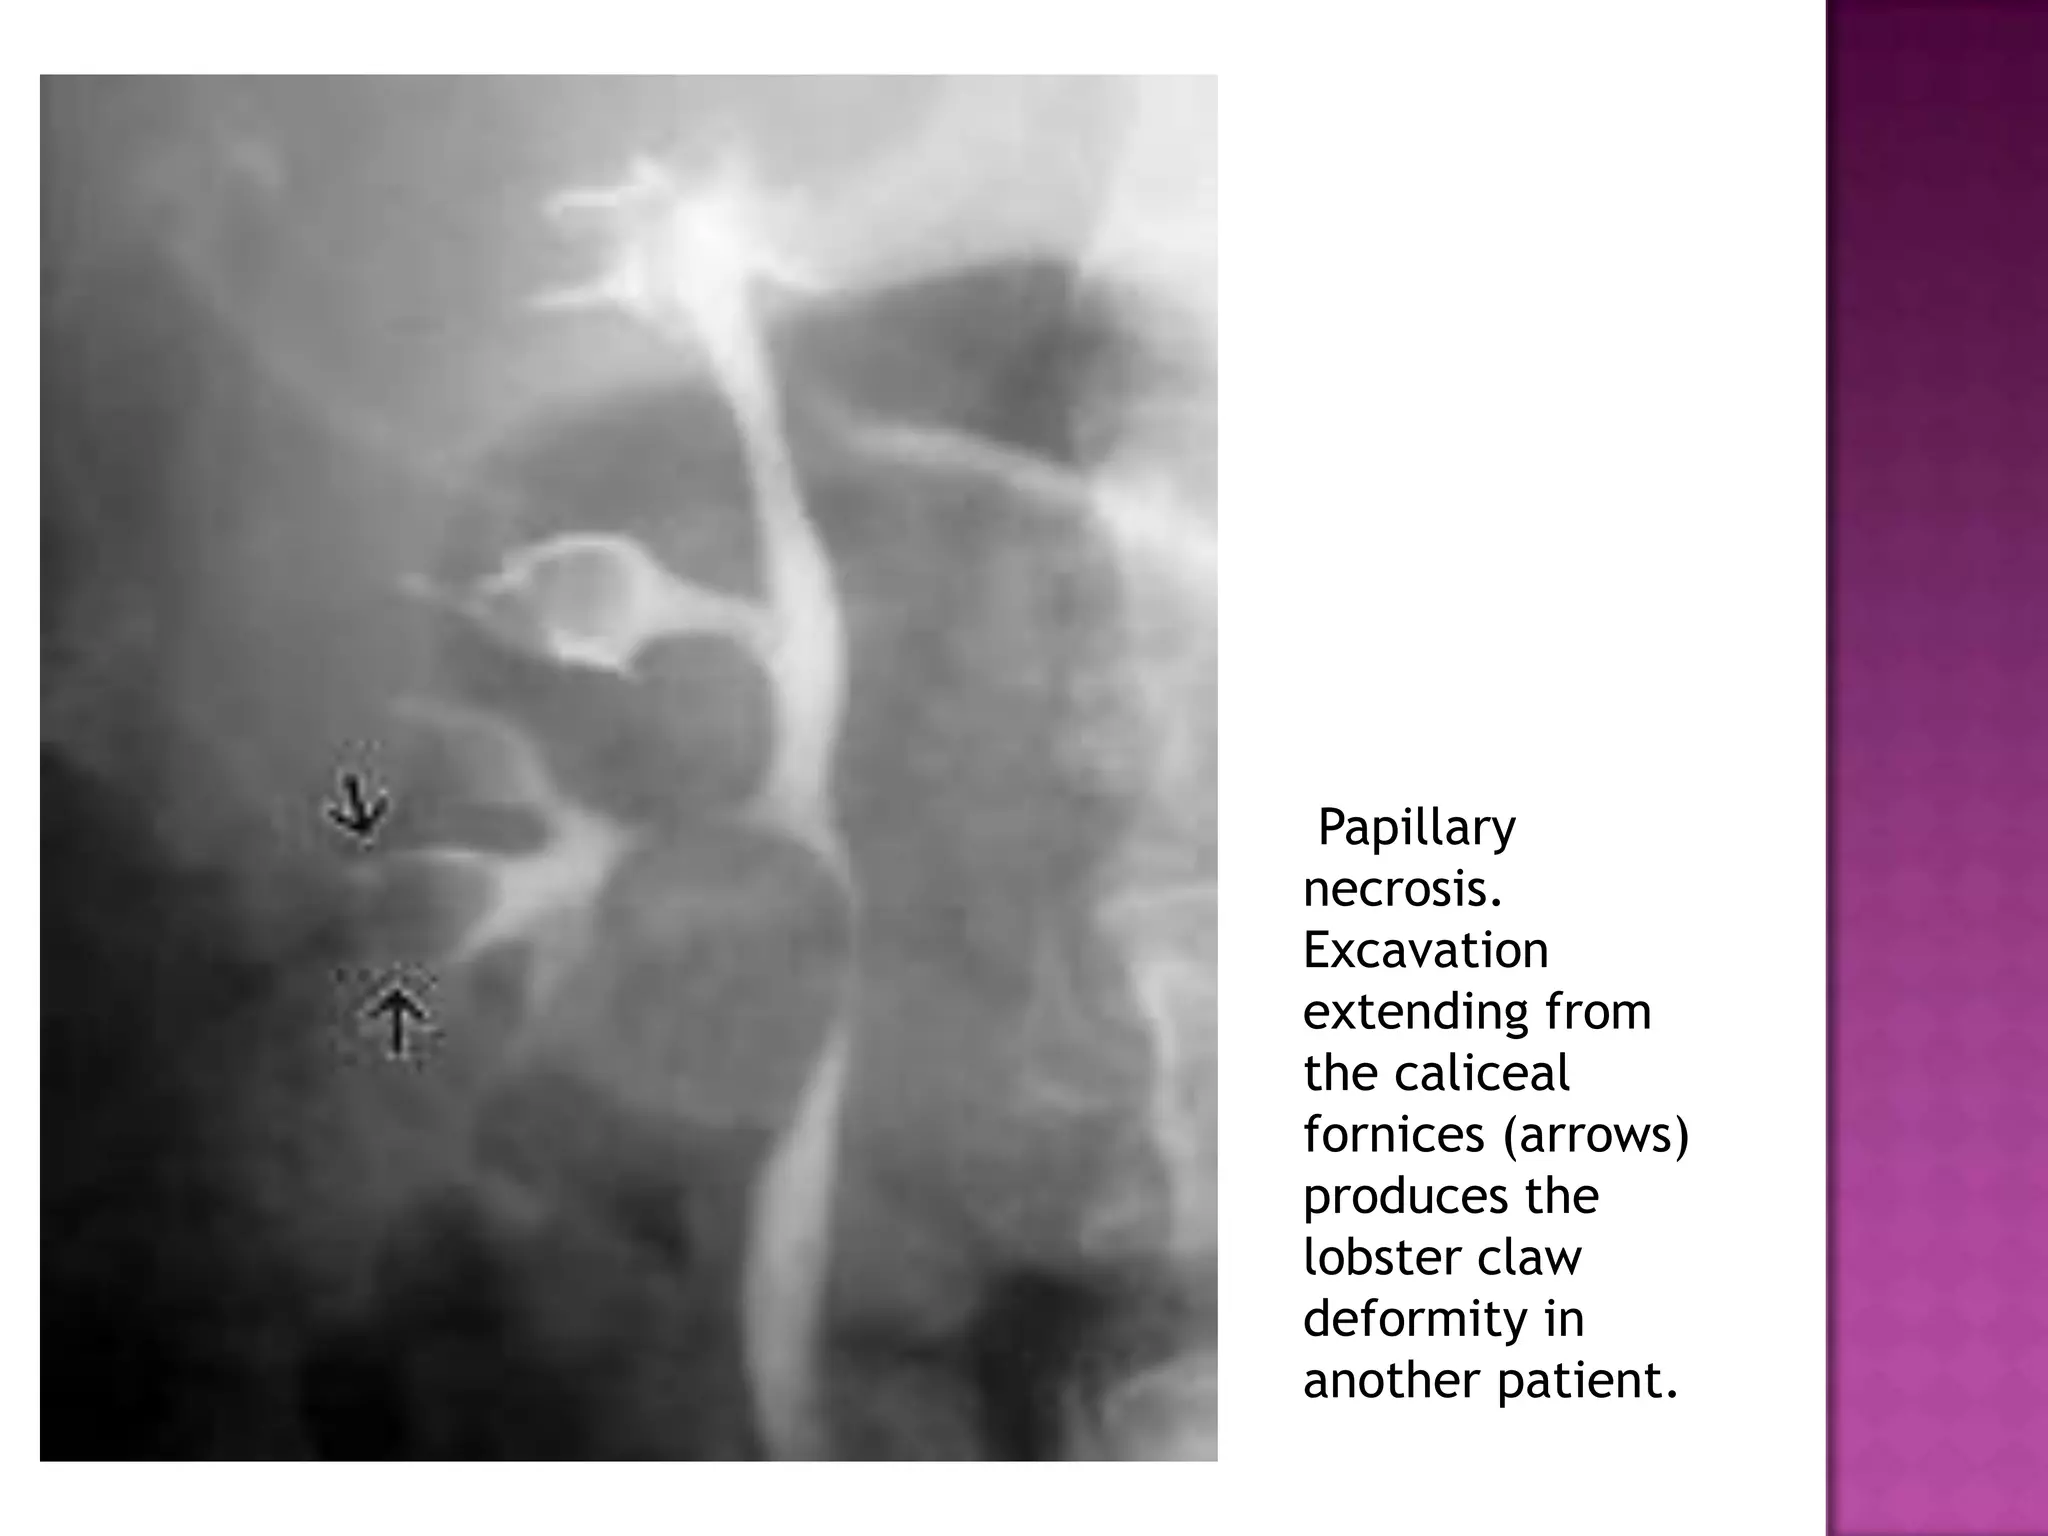

Papillary

necrosis.

Excavation

extending from

the caliceal

fornices (arrows)

produces the

lobster claw

deformity in

another patient.

Papillary necrosis. Excavation extending from the caliceal fornices(arrows) produces the lobster claw deformity in another patient.